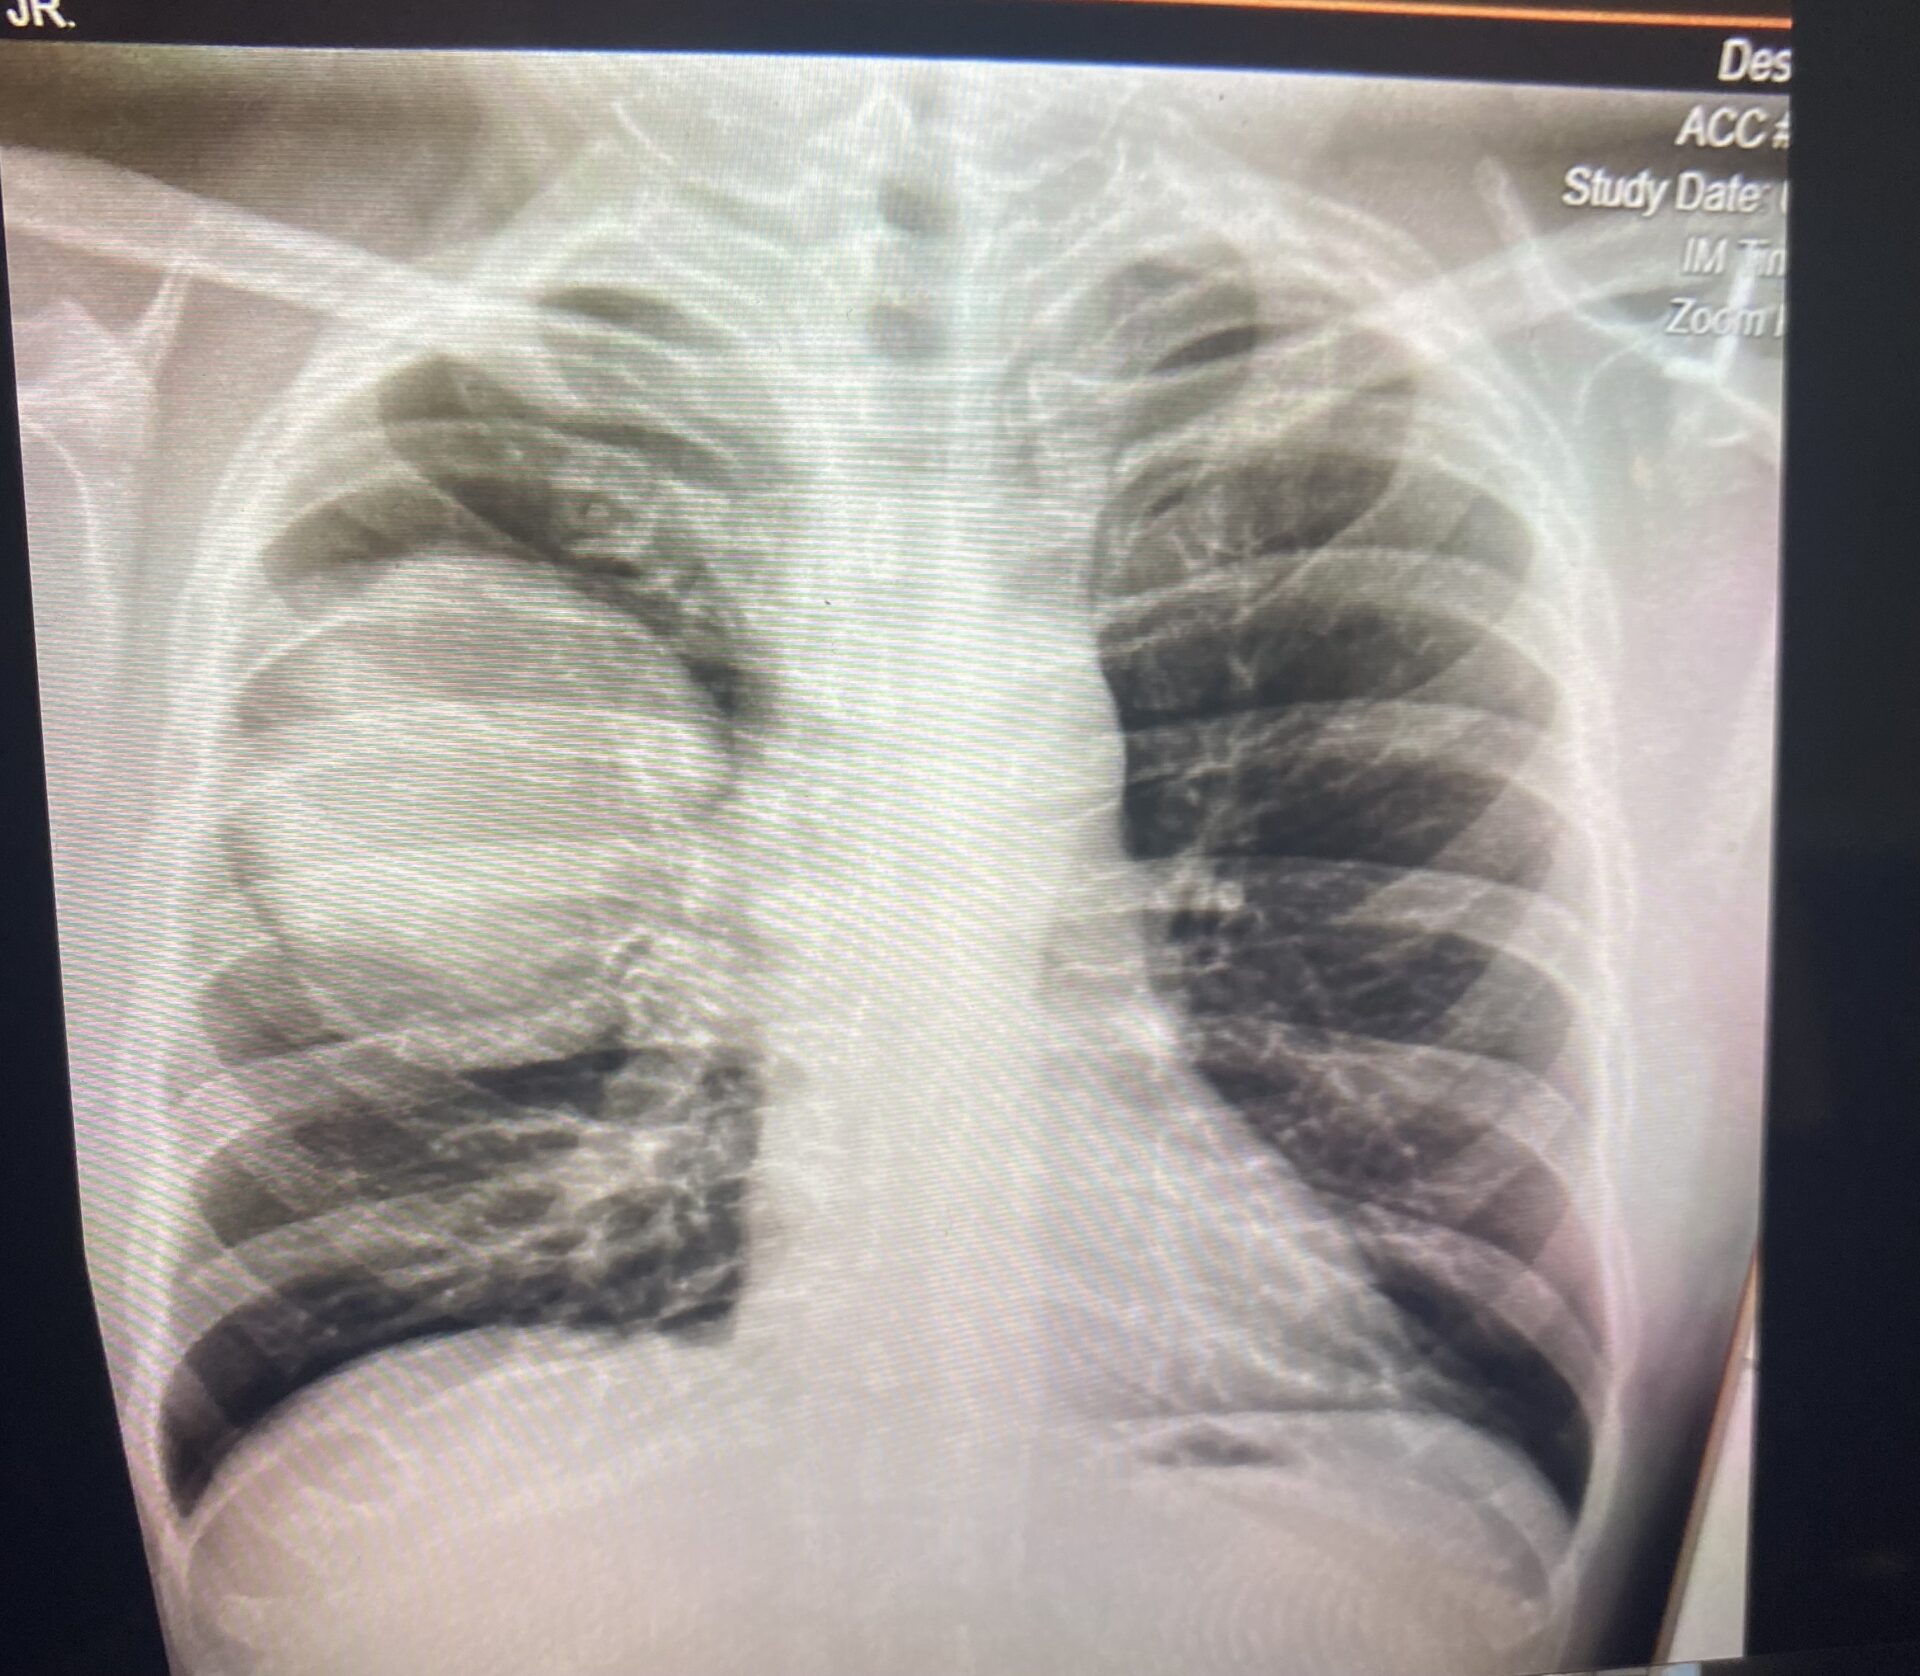

In the fall of 2021, however, Bill developed a persistent cough that worsened into trouble breathing. A chest x-ray revealed two masses in his chest. At the time, Bill was living in Virginia, but after learning the results, he made appointments in his hometown of Boston.

Bill was seen at Brigham and Women’s Hospital in Boston where another chest x-ray was taken.

“I walked around the corner and I’m met with a giant mass in my chest,” Bill said. “It literally looked like a cannonball in my chest. You don’t have to be a doctor to realize that’s not good.”